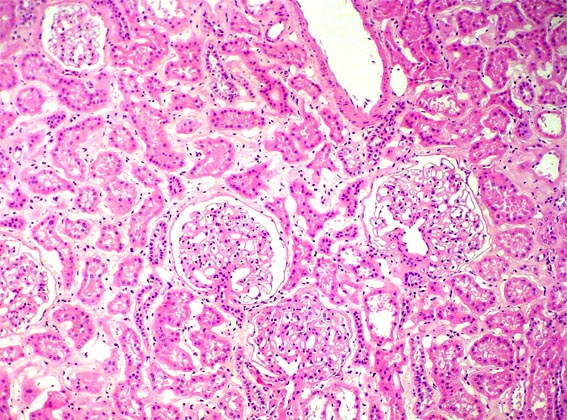

KIDNEY TISSUE:

Kidney tissue examples:

The Glomerulus, plural Glumeri, is a group of capillaries (tiny blood vessels) where waste is filtered from the blood.

kidney cells found in my slides: